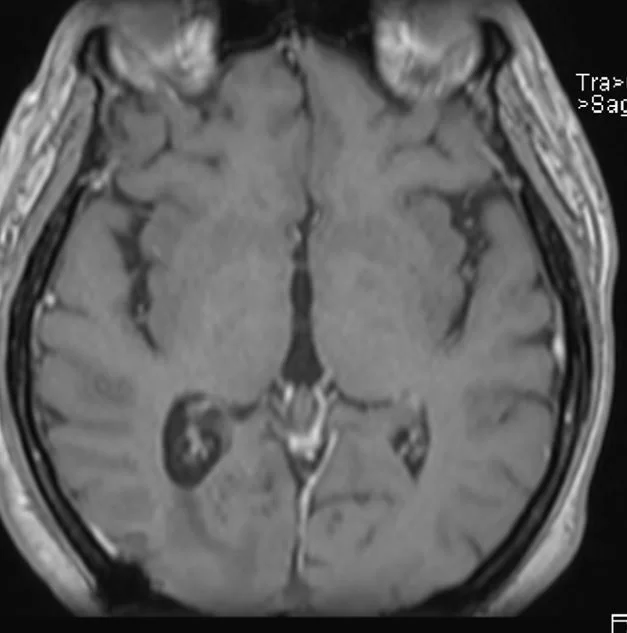

Η μετεγχειρητική αξονική τομογραφία εγκεφάλου δείχνει ολική εξαίρεση. Η ιστολογική εξέταση ανέδειξε μηνιγγίωμα (WHO I).

Οι μετεγχειρητική μαγνητική εγκεφάλου αναδεικνύει την ολική εξαίρεση της βλάβης